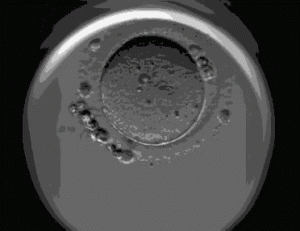

囊胚是胚胎体外培养的终末阶段,它通常形成形成于卵子受精后的第 5-7 天。自然状态下,人类胚胎以囊胚的形式植入母体,这样能获得较高的胚胎植入率。因为常规胚胎移植是在取卵后第三天进行,这时的胚胎含有5~8个细胞;而囊胚移植是指将胚胎在体外培养5~6天,含约数百个细胞,形成囊胚后再植入子宫腔。这么说来似乎囊胚移植要好的多,但并不是所有人都适用!来了解下:

胚胎细胞分裂,最后形成囊胚